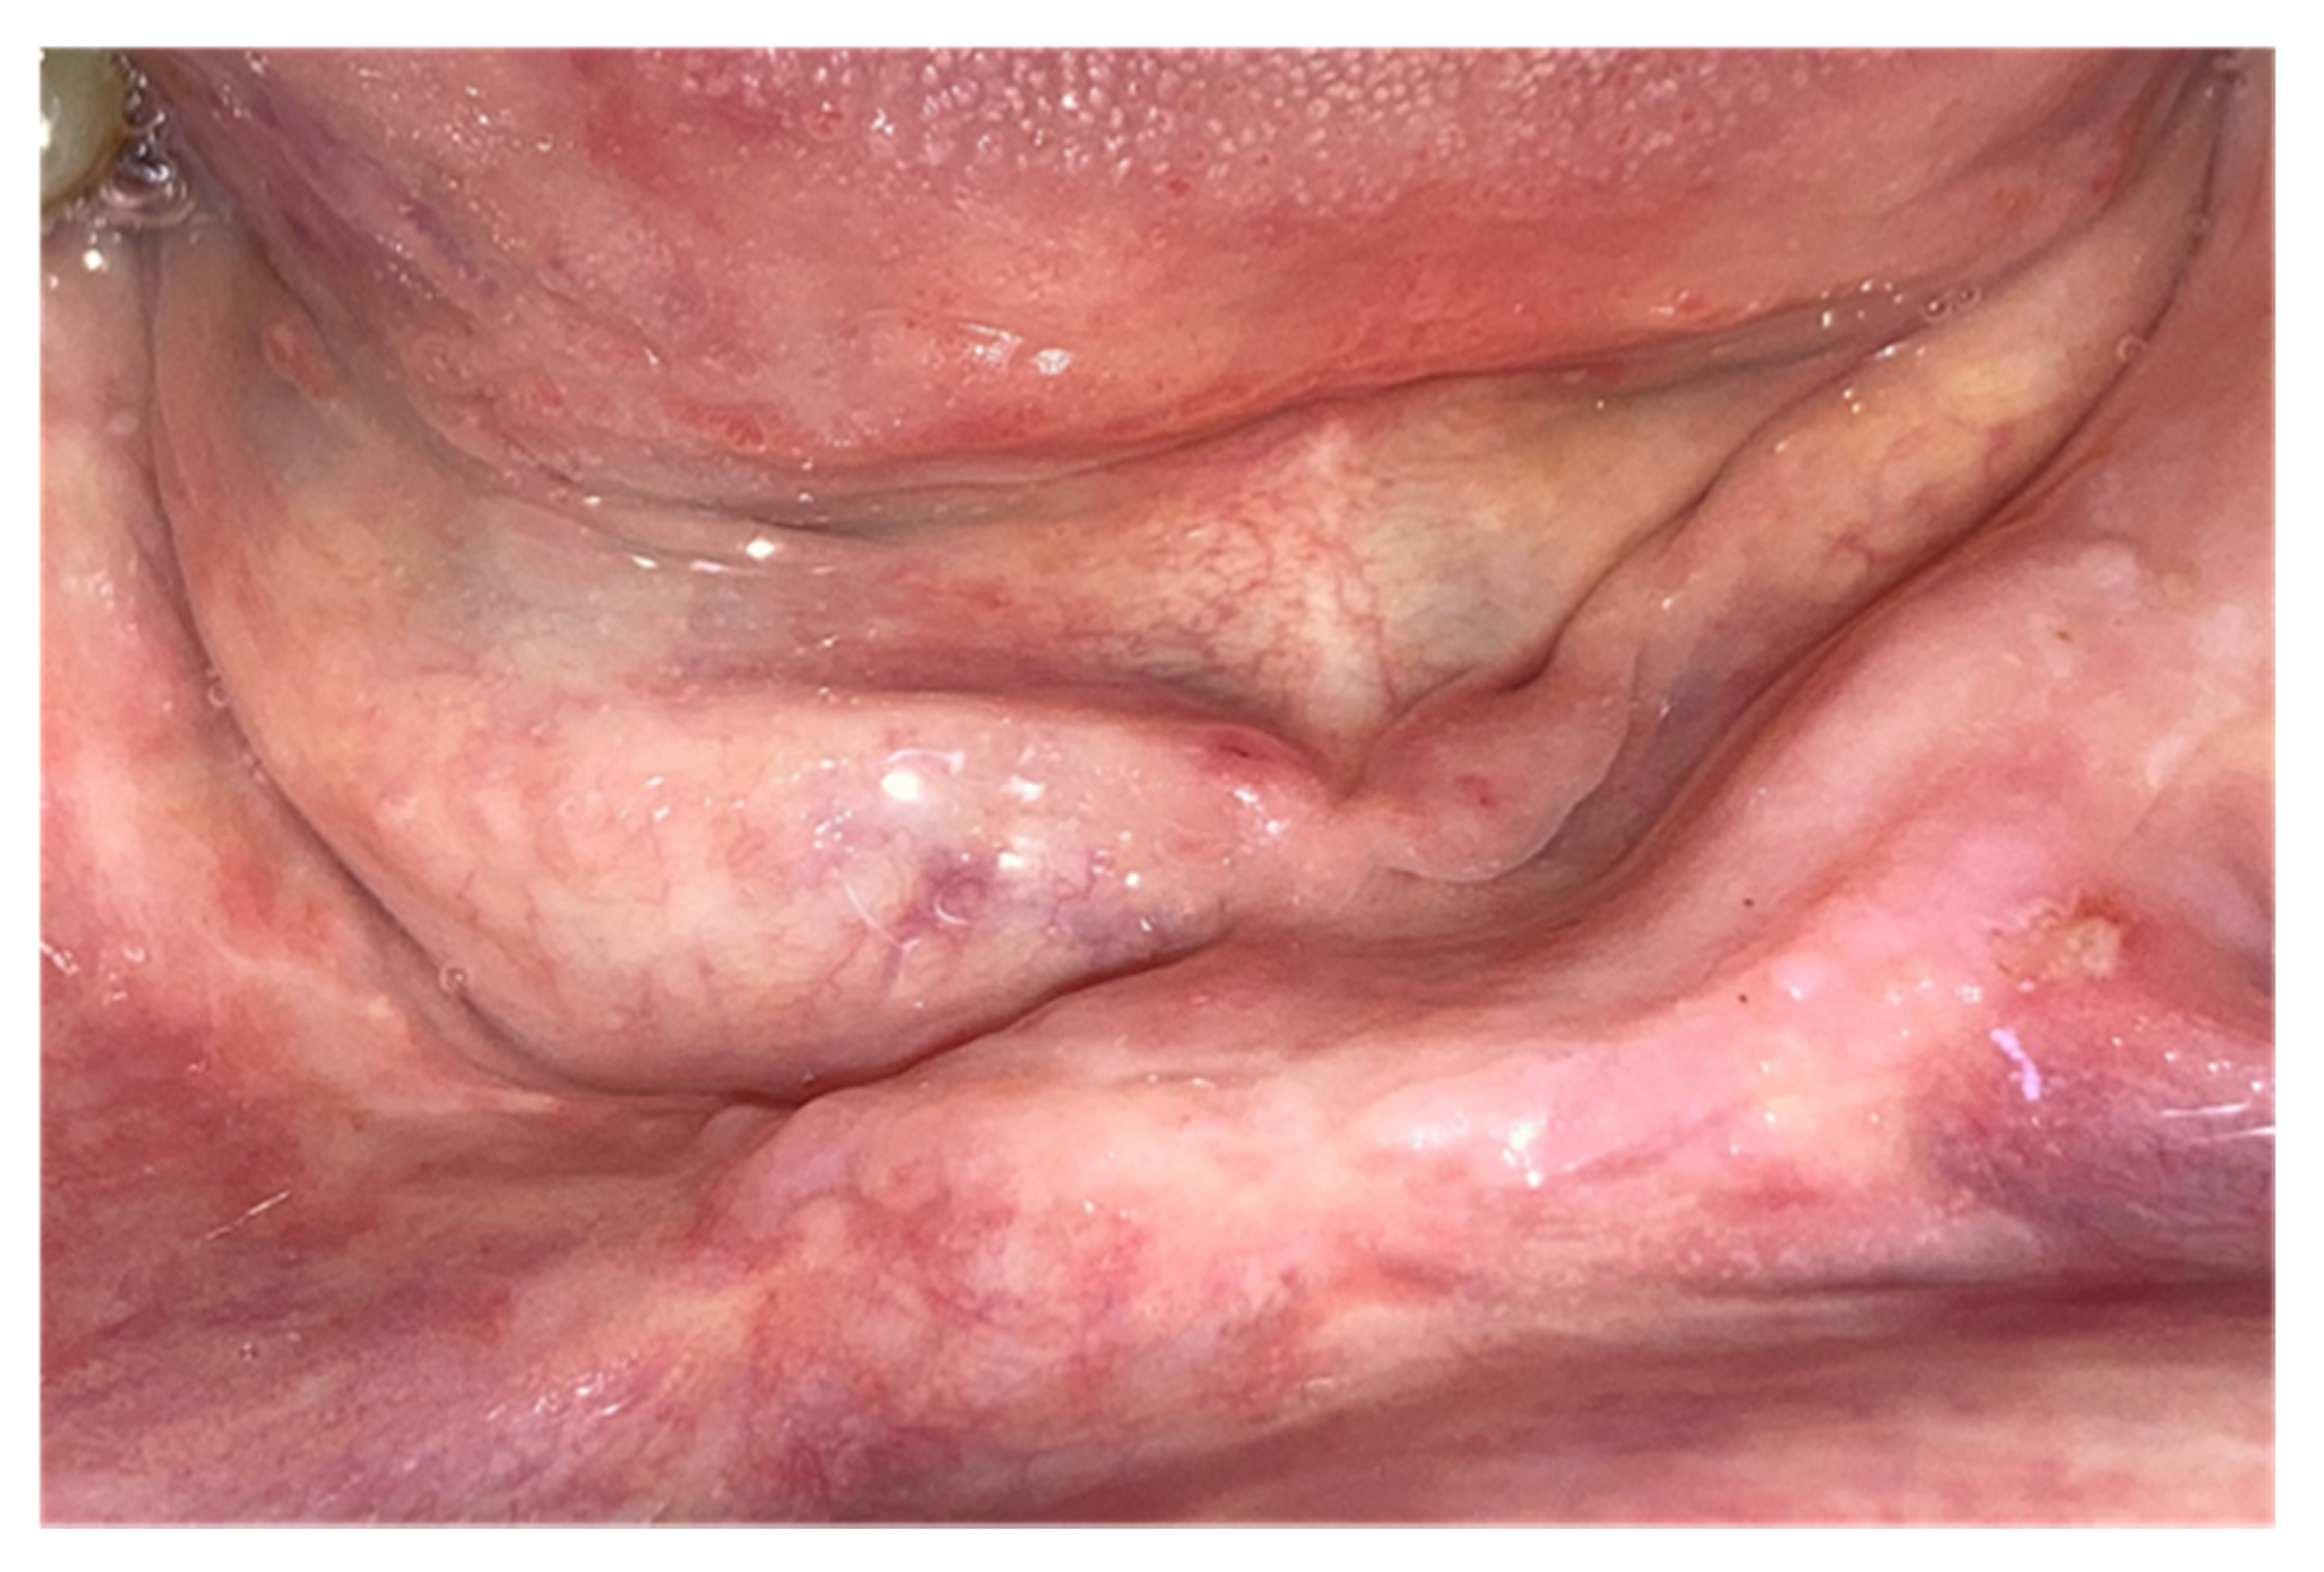

| Outcome | ||||||||

| Spontaneous expulsion of sequestrum | x | 1 | ||||||

| Healed | x | x | x | x | 4 | |||

| Partially healed | ||||||||

| Unchanged | ||||||||

| Progressive | x | 1 | ||||||